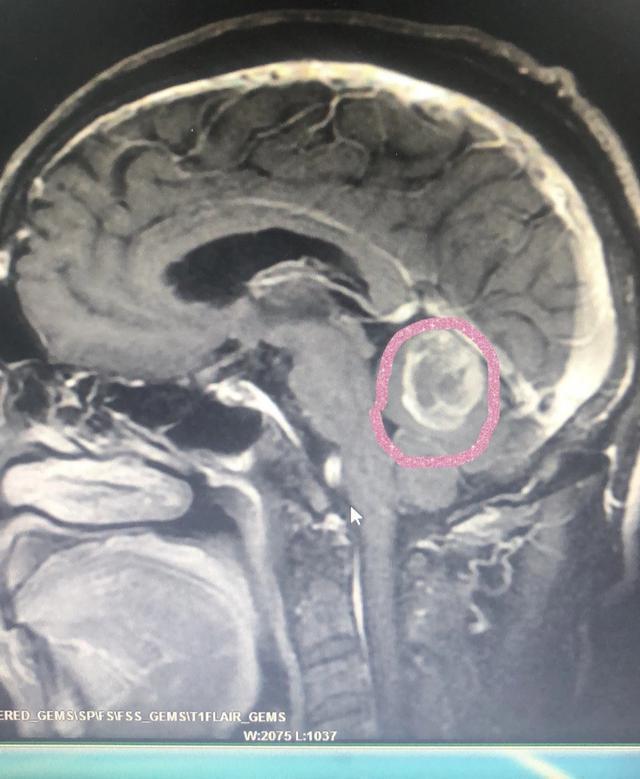

这张图片是我接诊的一位63岁老年患者、患者以眩晕、呕吐、走路不稳为首发症状入我院神经内科、进一步检查发现双肺多发肿块,小脑肿块、考虑肺癌脑转移转入我科。

患者双肺典型多发转移灶,下图被我圈出来的是其中一个转移灶。